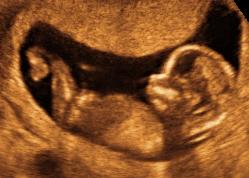

Nu ved jeg ikke, hvor i landet du er blevet scannet, men med mit første barn blev jeg scannet på Frederiksberg Hospital, og der slukkede sygeplejersken for skærmen efter 20 sekunder og sagde, at hun havde en stærk mistanke om misdannelser, men at det skulle bekræftes af en overlæge på Rigshospitalet. Hun gav altså klar besked med det samme trods en lille usikkerhed, og det er min overbevisning, at de frem for alt er ærlige - ens tanker er ofte endnu værre end virkeligheden, fik vi at vide, så de vil gerne have, at man er informeret om altid. Vi skulle vente en dag på næste scanning, men fik en masse info om, hvad vi skulle gå hjem og læse om på nettet, så vi kunne være forberedt.